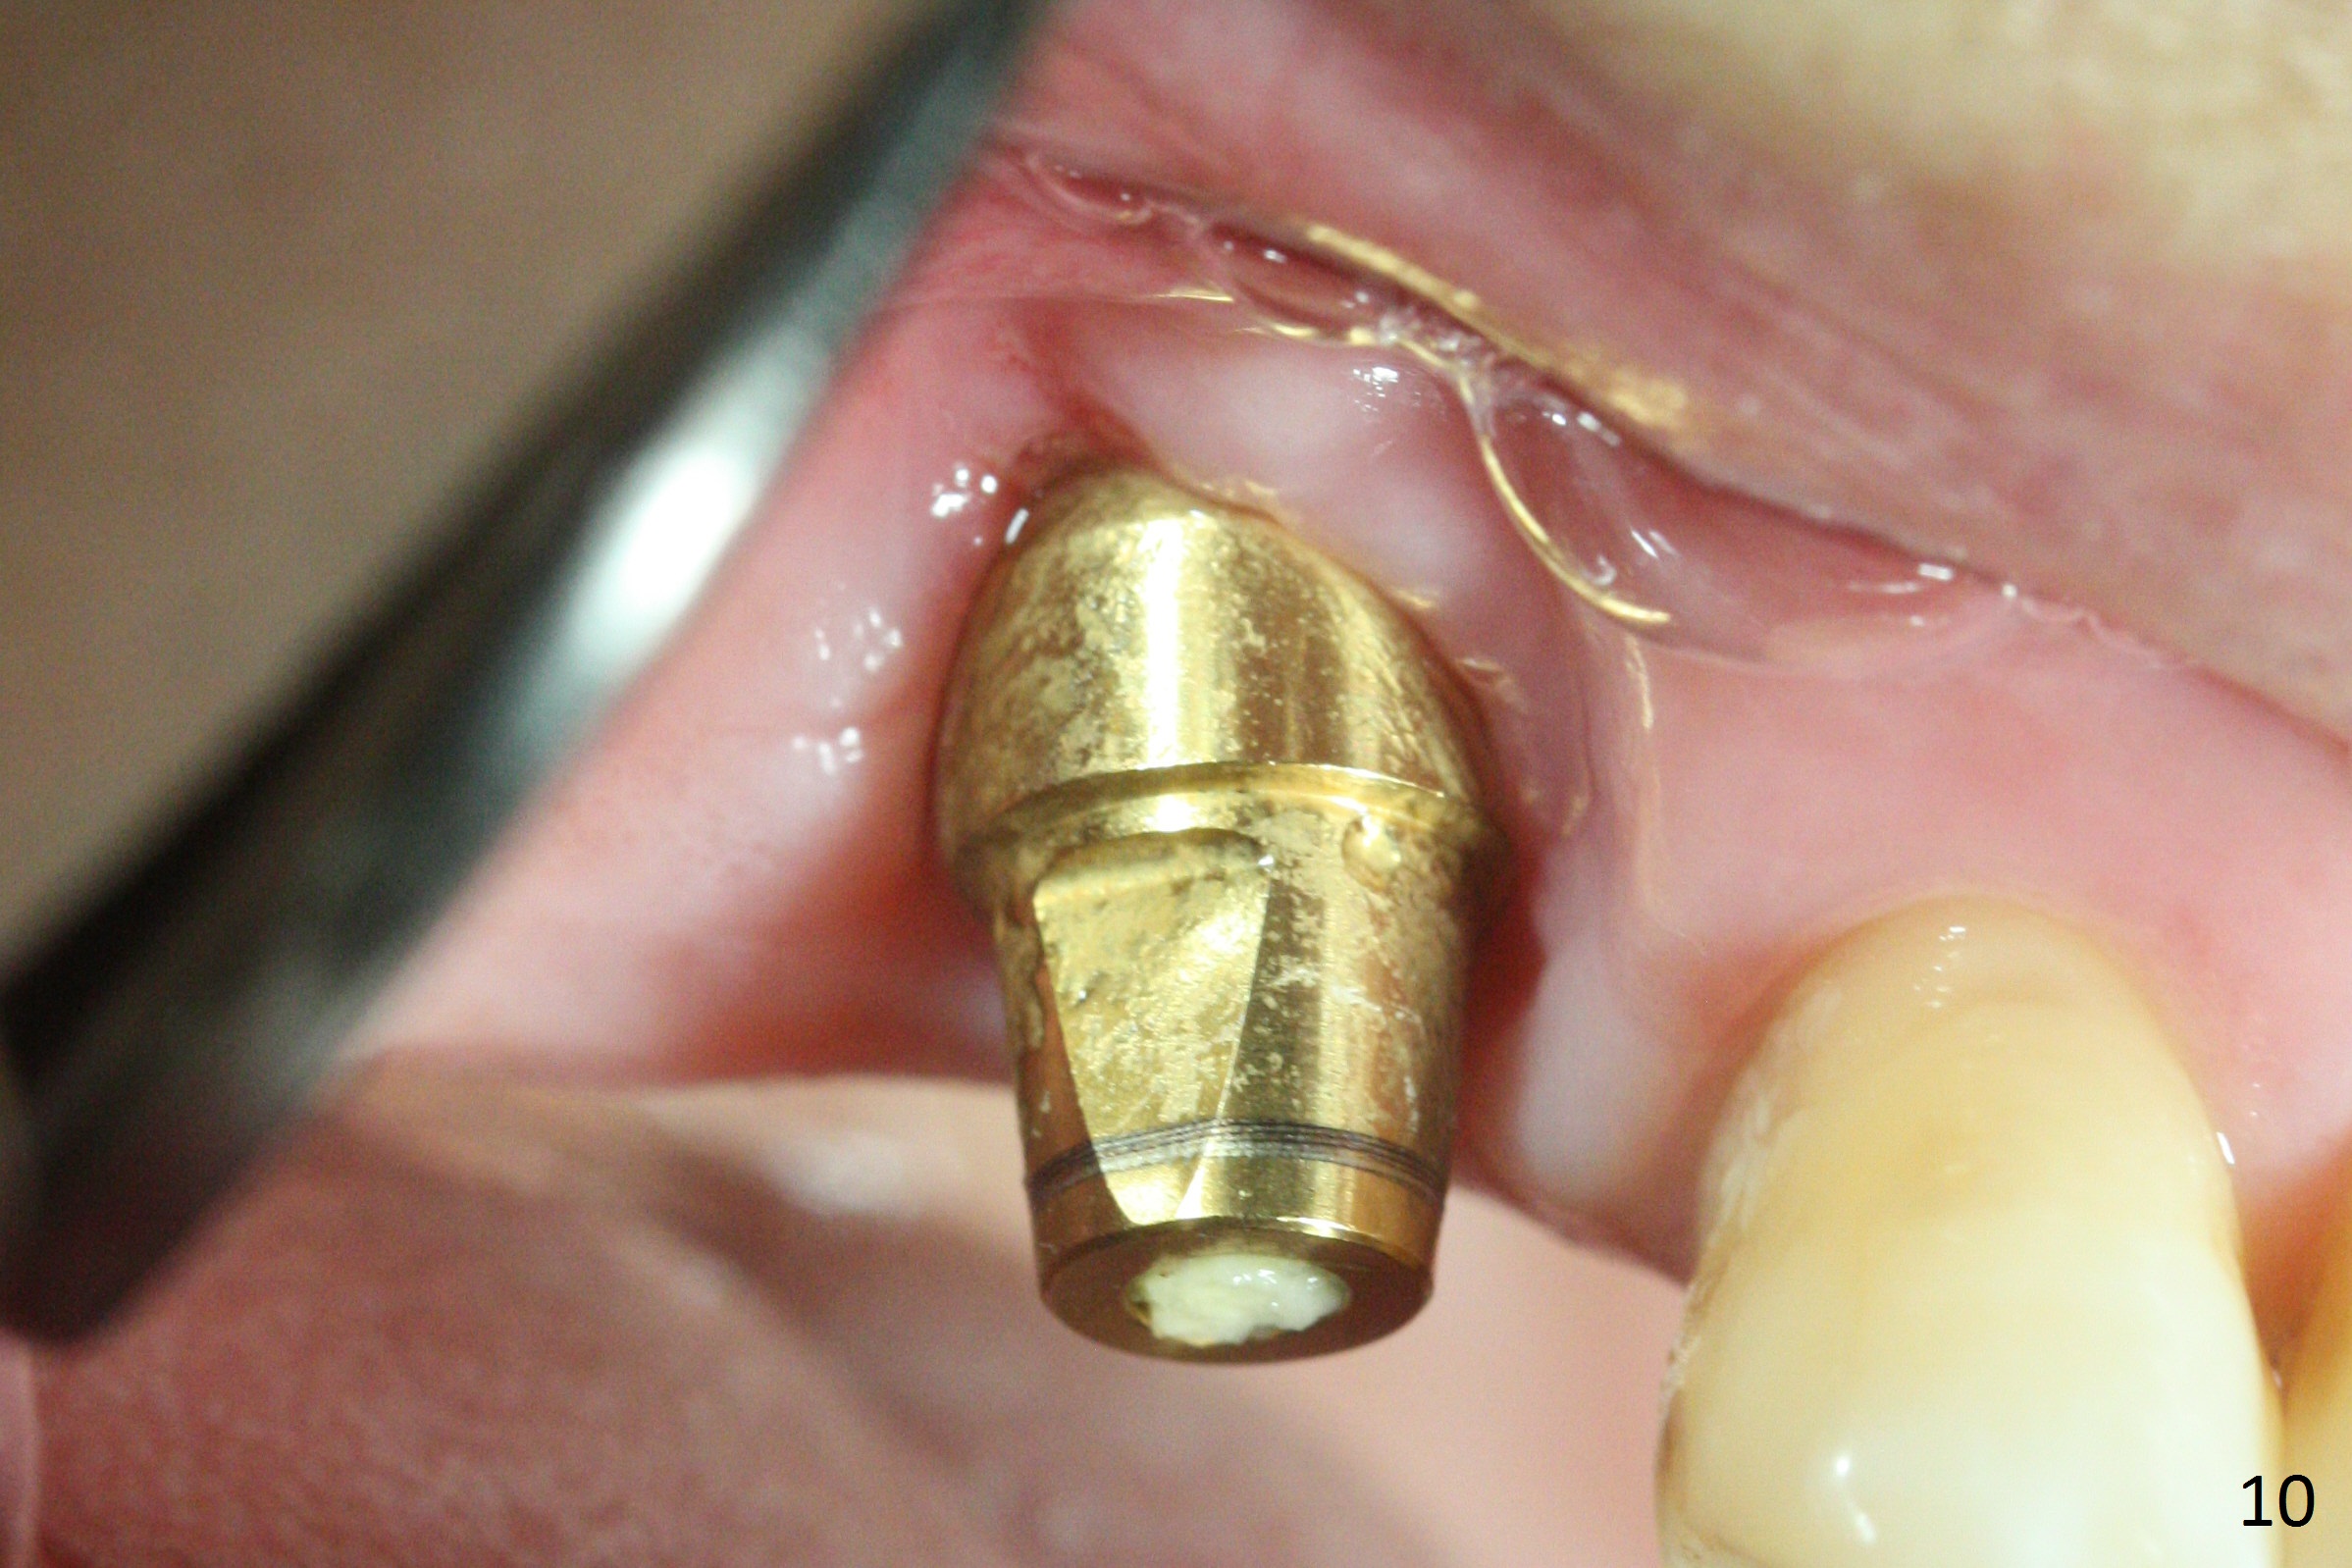

The buccal margin remains supragingival (Fig.10), while the palatal one subgingival 1.5 months postop (Fig.11 P). The abutment is changed to 4.8x7(3) mm (Fig.12). A provisional is fabricated to keep the palatal space for easy impression later on. With the smaller abutment and less tension, the buccal gingiva is expected to grow more coronal to reduce recession.